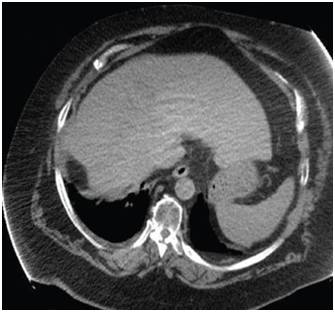

患者男性,65岁。2014年10月,患者感到腹部不适、头疼。检查和诊断结果为(1)高分化肝细胞癌,大小约10cm,肝硬化明显。(2)脑转移瘤,左枕叶处有大小约3cm的肿块。(3)II型糖尿病,需要胰岛素治疗。(4)慢性肾病;(5)中度高血压,有心衰病史。

患者处于肝癌晚期,肝癌病灶巨大且有脑转移,国内医疗机构不能实施外科手术治疗。经全球肿瘤医生网请国际癌症专家组远程咨询,患者定于2014年11月10日出国进行EDGE速锋刀无创手术治疗。先后对肝脏肿瘤和脑转移瘤进行EDGE治疗,在医院共治疗8天。每个肿瘤每天治疗1次,每次治疗时间约10分钟左右,肝脏肿瘤共治疗6次,脑肿瘤治疗4次。患者手术过程中无任何不适,每次治疗后正常回公寓休息。半年后,患者身体状态良好,体重明显增加。影像检查报告显示肝脏的巨大肿瘤被彻底清除,脑部肿瘤几乎完全消除,且没有复发。生化检查结果表明肝功能未见异常。

肝脏肿瘤治疗前10cm

肝脏肿瘤治疗后完全消除